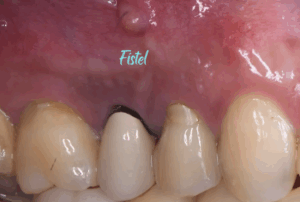

医院ブログ 2026/03/08

【表参道 歯科 ダイレクトボンディング】 破折した... こんにちは。表参道・青山にある歯科石上医院です。 自転車の交通事故…